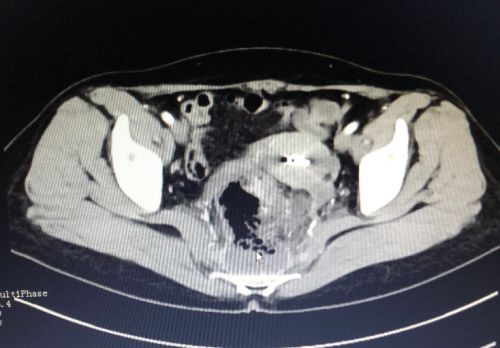

影像上可以看到气体和脓肿(鼠标所示)。

入院后,刘祺主任医师为吴女士进行肛门指检,发现直肠有脓肿,考虑为直肠穿孔。CT检查发现,本应在肠道内的气体跑出肠子到了骶前位置,进一步证实了直肠穿孔的诊断。